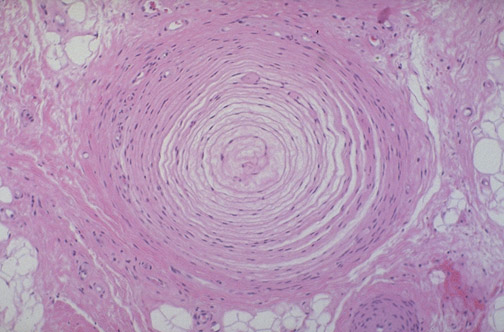

| The dermis of the skin contains many specialized nerve endings that provide for sensation. Most can only be identified with special staining techniques, but here is one large enough to view with a routine H&E stain. Seen here at high magnification is a pressoreceptor known as a Pacinian corpuscle. This pressoreceptor happens to come from a toe, where pressure sensation is critical to balance and movement. |